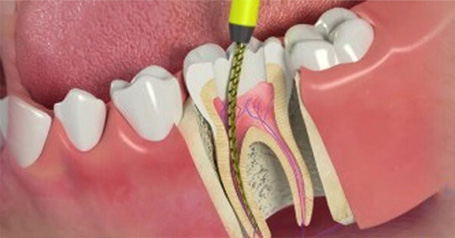

A root canal is a dental procedure that removes the infected or damaged pulp from inside your tooth, cleans and disinfects the area, and then seals it. This helps save your natural tooth and prevents the need for extraction.

4. Shaping & Filling the Root Canals

The infected pulp is removed and the tooth is filled with root filling

If the nerve of a tooth has become decayed or infected, a Root Canal may save the tooth itself whilst removing the problematic root. The nerve part of the tooth, along with the pulp (living tissue inside the tooth) and any bacteria or decay present is removed; then the tooth is sealed with special root-filling cement all the way to the tip of the root. This will save your tooth once the root is filled and sealed properly to the very apex; and it gets rid of the painful soft tissue and leaves a hard shell. A dental crown is then fitted to ensure the tooth has full functionality within your mouth.